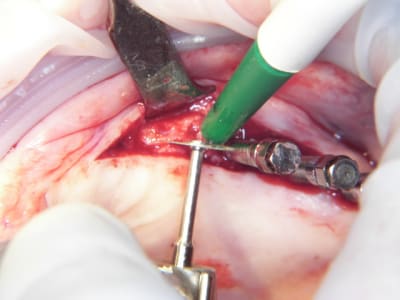

15/07/2009 à 21h13

Pas cool le début de semaine.

1 patient trompé d'heure, reporté.

Deuxième cas je n'ai fait qu'un coté car le papy fatiguait (pas moi, le patient)

Pose d'implant court ce qui n'est pas ma tasse de thé, mais il ne faut pas mourir idiot, alors.

Un 103.4, un 6.5x4.6, un 8x4.6 et un 8x3.4

Première pour moi avec le nouvel Axiom d'Anthogyr.

Je n'étais pas sur de pouvoir utiliser la technique avec implant lisses, mais si.

Implants légèrement coniques, autoforants, outils trilobé et non pas 8 pans creux.

Pas eu de problèmes particuliers, il faut attendre pour le résultat.

Seul point il faut faire attention au vissage qui conditionne la position du cône morse.

Globalement j'ai bien aimé, même si je n'ai pas été aussi fabuleusement génial que d'ab dans la réalisation..........

Merci pour cette expérience partagée. Belles photos. Merci aussi d'avoir l'honnêteté de présenter un cas qui ,s'il paraît franchement parfait sur les photos de chir, l'est un poil moins sur la pano (mais c'est qu'une pano). De toute façon avec une expérience comme la tienne la gestion prothétique se fera sans doute sans trop de soucis.

Sympa aussi l'utilisation de ton "écarteur de lèvres". Je l'avais eu en échantillon il y a quelques temps mais je pense qu'une de mes assistantes avait dû croire que c'était du jetable et pas moyen de me souvenir ou les trouver.

Peux-tu nous indiquer les références ? C'est bien stérilisable ? J'achète dès ta réponse.

pour la prothèse, je ne me fais pas de souci mais la pose sur le pano me plait tres moyennement, alors qu'en bouche ça paraissait axé comme il faut.

les ecarteurs se sont des optragates de chez ivoclar et ton AD avait raison c'est du jetable.

il doivent les sortir en steriles mais pour le moment ils sont en emballage individuel, je les fait tremper dans la betadine.

ils sont bien, faut pas se planter sur la taille, là on a changé en cours d'intervention et penser à coller le champs dessous et non pas sur l'optragate sinon il tient mal

sinon il y a aussi l'optiview de Kerr qui est pratique, mais moins couvrant